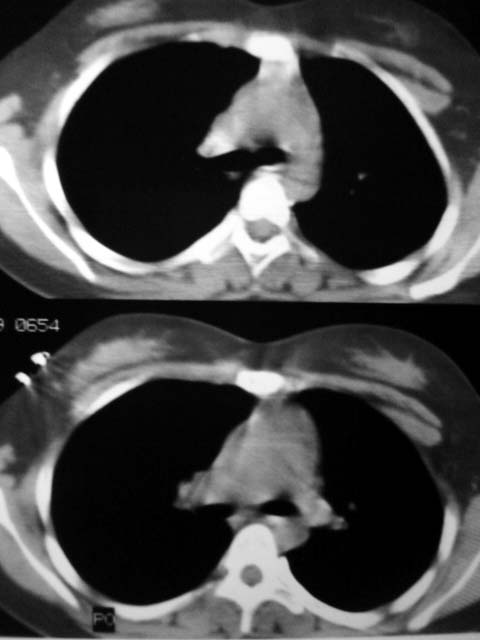

标题: CT12463:女,19岁,炎性假瘤?结核球? [打印本页]

女,19岁,体检时发现。炎性假瘤?结核球?

早产儿,幼时体弱,常感冒肺部感染,13岁后好转。两月前“感冒”后咳嗽两周。

纵隔窗肿块明显较肺窗小,切粗长毛刺,“倒核桃”征:考虑炎性假瘤

病灶肺纵比较大,边缘平直,周围无卫星灶,考虑炎症。建议抗炎治疗后复查。

考虑炎症,抗炎后复查。理由:病变肺窗显示的大小明显大于纵隔窗,提示病变周围为密度偏低的渗出改变。不同于结核球和肿瘤。